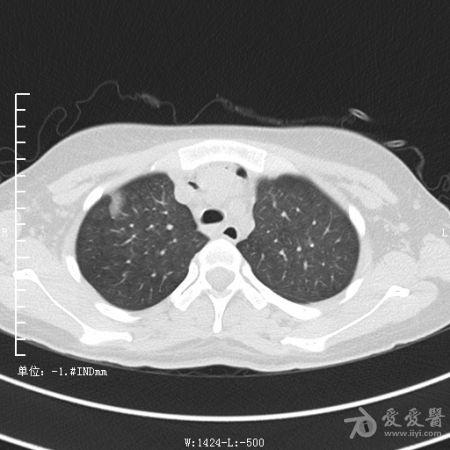

典型支气管扩张及肺水肿CT片

典型支气管扩张肺水肿